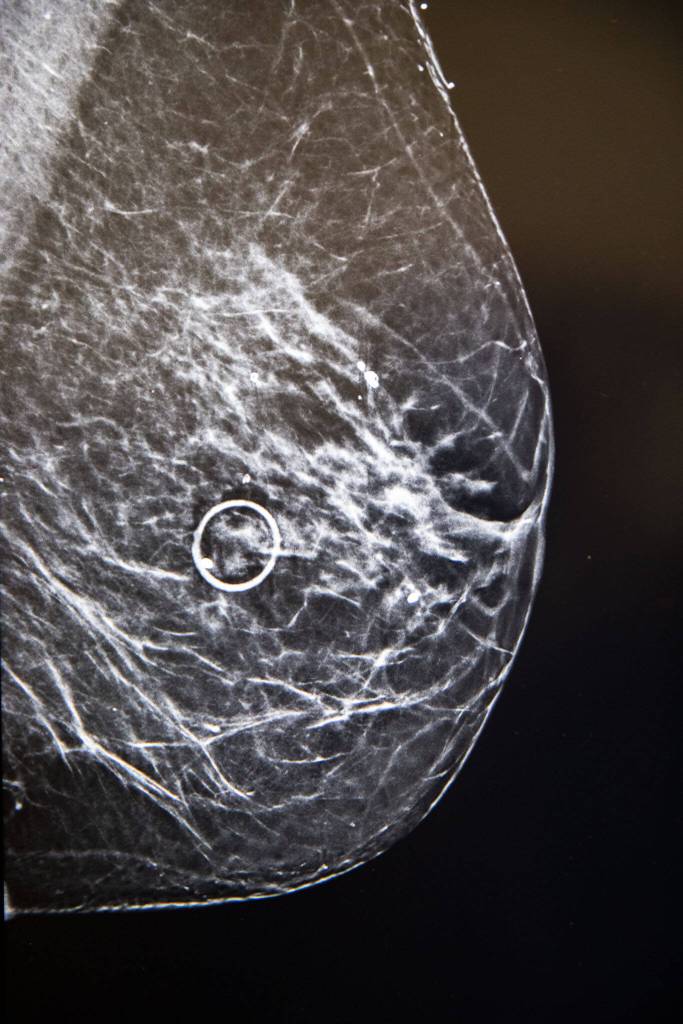

The program serves as a safety net for patients who may have cancer that goes undetected in regular mammograms, which miss about 1 in every 8 breast cancer diagnoses, according to the American Cancer Society. Patients with dense breast tissue are more likely to get false-negative results.

Now, when patients age 25 to 80 schedule a mammogram at the Comprehensive Breast Center, they can fill out a 10-minute personal and family history survey sent to their emails. The tool provides an instant cancer risk assessment. If a person is 20% at risk or higher, the tool also recommends next steps such as saliva-based genetic testing, magnetic resonance imaging (MRI) or a contrast-enhanced mammography that can detect cancer in dense breast tissue.

To support the early detection program, Pink Ribbon Row and the Providence General Foundation granted $116,000 for contrast-enhanced mammography equipment. The technology is faster, cheaper and easier for insurance approval than an MRI.